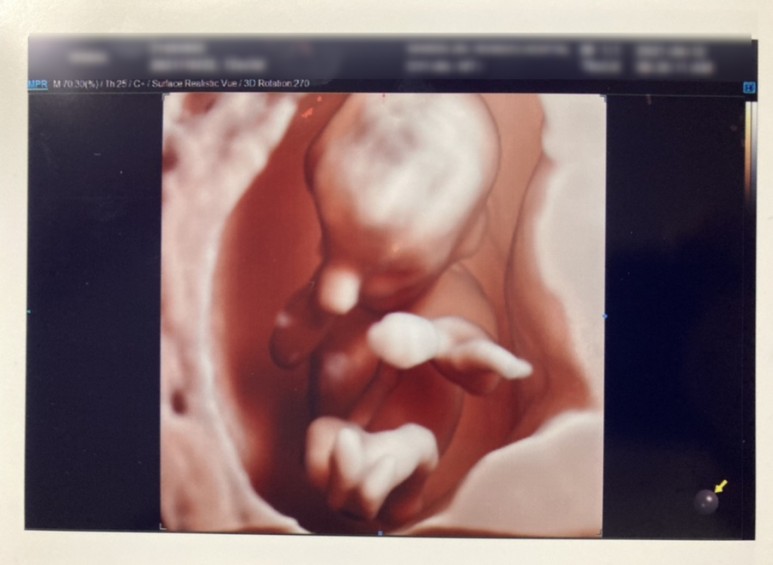

두 다리를 꼬고 막은 한방이 ㅋㅋ1차 기형아 검사라니?보통 태아의 목구멍 투명띠가 가장 뚜렷하게 보이는 시기인 11주~12주 사이에 실시하는 검사로 태아의 목구멍 투명띠의 넓이를 측정하는 검사입니다.이 검사로 다운증후군 같은 염색체 기형을 가장 빨리 알 수 있대요.병원마다 약간의 기준 차이는 있지만 보통 2.7mm~3mm를 기준으로 한다고 합니다.:) 기준치 이상이 나와 고위험군으로 나오면 정밀검사(니프티 검사, 양수 검사 등)를 권한다고 합니다.취약x증후군 선별검사?취약 X 증후군이나 지능 저하 및 학습 장애를 나타내는 유전성 질환이라고 합니다.산모의 혈액에서 DNA 검사를 통해 유전자 분석을 해 아이의 정신지체 여부를 미리 예측하는 방법으로 검사는 의외로 간단하고 필수검사가 아니라 선택검사로 보통 첫 아이를 가진 산모가 많이 한다는 것이다.이 검사는 첫 번째 임신 때 하면 둘째 때는 안해도 된대요!! 병원에서도 첫째면 할 걸 권해줘서 고민하다가 남편이 옆에서 하라고 해서 그냥 해ㅋㅋ(내가 다니는 병원에서 가격은 7만원!) 사실 집에 이런 질환을 가진 사람도 없고, 요즘 몇몇 임산부가 검사를 하는데 많이 하는 것도 아니고, 아직 나이도 어린 편?그래서 노산도 아니니까 그만두려고 했는데 막상 병원에서 추천해주니까 할 수 밖에 없네요.

한방이 목구멍 투명대의 검사결과는!! 1.4mm로 무사통과~ 초음파선생님이 콧대와 함께 좌뇌, 우뇌도 확인해주었다.지난주에 초음파 봤을 때는 즐겁게 움직이던 한방이 이번엔 고개를 돌리고 얌전히 있어서…목 투명대를 정확히 측정하기는 어렵다며 초음파검사 선생님이 배를 꾹꾹 눌러도 꿈쩍도 않던 한 방이 큭큭큭큭큭큭큭큭큭큭큭큭큭큭큭큭큭큭큭큭큭큭큭큭큭큭큭큭큭큭큭큭큭큭큭큭큭큭큭큭큭큭큭큭큭큭큭큭큭큭큭큭큭큭큭큭큭큭큭큭큭큭큭큭큭큭큭큭큭큭큭다음 진료는 4주후 2차 기형아 검사!! 그 동안 정기검진은 2주마다 있었는데 한방을 보고 싶다고 매주 병원에 갔었는데, 벌써 2주마다 가야해…